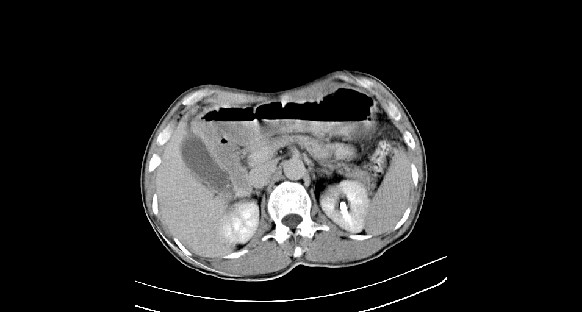

男性,70岁,体检b超发现左肾占位,请各位战友发表一下观点

左肾有两个病灶,且较大的病灶内可见点状钙化灶,增强扫描边缘也是呈渐进性强化,中央部分未见明显强化